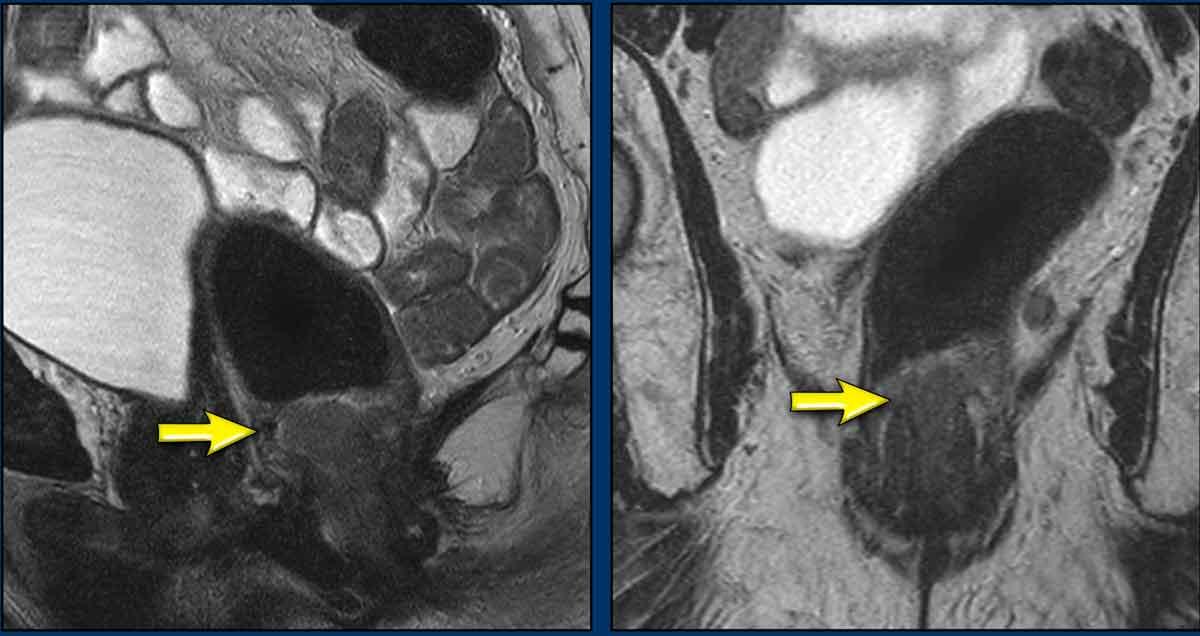

Hình ảnh

Đây là hình ảnh ung thư hậu môn trước hóa xạ trị.

Tiếp tục xem hình ảnh sau điều trị…

Hình ảnh sau CRT

Ghi nhận đáp ứng hoàn toàn với chỉ một vùng xơ hóa mỏng nhỏ tại vị trí khối u cũ ở vị trí 1-3 giờ trong cơ thắt trong (mũi tên).

Không có dấu hiệu hạn chế khuếch tán (cuộn ảnh).

Phần còn lại của cơ thắt trong cho thấy tín hiệu trung gian đến cao mờ nhạt, biểu hiện phù nề do xạ trị (không có hạn chế khuếch tán).

Tiếp tục xem hình ảnh sau 2 năm…

Ghi nhận tái phát tại chỗ 2 năm sau khi hoàn thành CRT.

Lưu ý rằng tổn thương tái phát có kích thước lớn hơn khối u nguyên phát.

Cần thực hiện phẫu thuật cắt bỏ bụng-tầng sinh môn mở rộng sau khi xạ trị lại để cứu vãn trường hợp tái phát này.